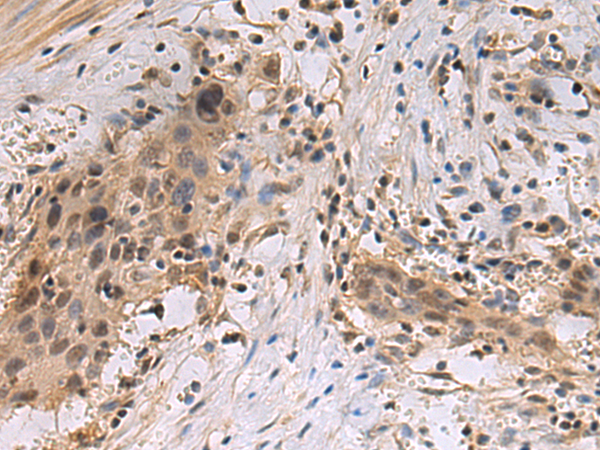

分类: 科研抗体货号: P13579别名: HLA-DR1B; HLA-DR3B应用: WB,IHC反应种属: Human